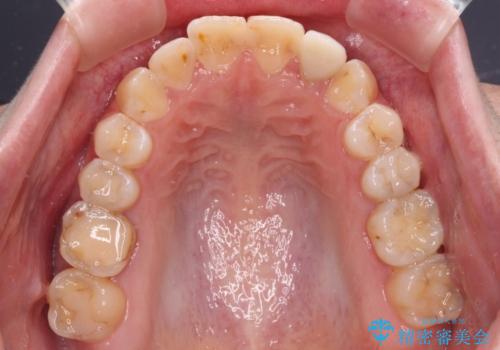

開咬を治す インビザラインによる矯正治療

- 上下前歯の開咬を気にして来院された患者様です。

開咬はインビザラインを用いると有意に改善ができるため、インビザラインによる矯正治療を行うこととしました。

途中1年8ヶ月ほど来院されず、久しぶりの来院後は治療が面倒とのことで、前歯の叢生や隙間に不十分な点が残った状態での終了となりました。